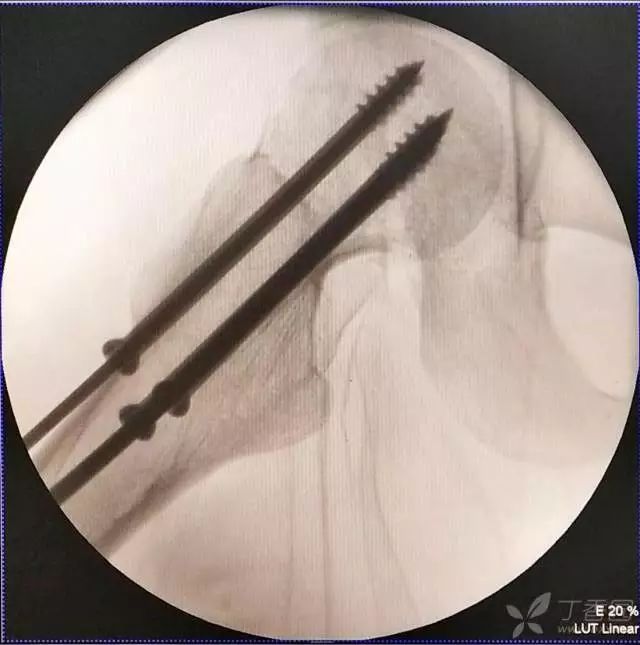

6. 然后依次打入倒品字上方的两枚导针

7. 摆 4 字位检查侧位导针的位置是否恰当

打第 2、3 枚导针有个小技巧,首先用导向器套住第一枚导针判断合适的距离,以及上方两枚导针之间的距离,此时顺着导向器插入第 2 枚导针。

这里需要注意的是,不是沿着导向器直接打进去(这样往往打入的导针无法与第一枚导针平行,不好看),笔者会稍打进去一点能把针固定住就好,然后把导向器退出来,看体外针尾平行方向往里打。这样确实打出来的导针都比较平行。最后把第三枚导针按第二枚的步骤打进去就可以了。